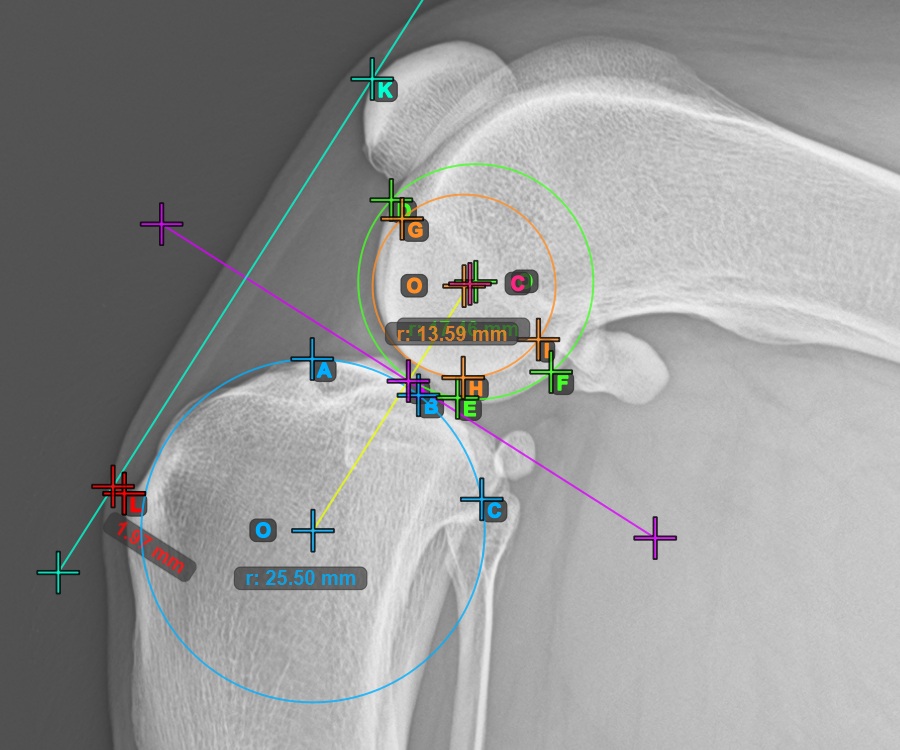

The image below represents a typical placement of the point on the common tangent between the two circles.

Start the TTA measurement procedure by marking the most cranial point of the Patella.

The image below depicts the usual placement of the most cranial point of the Patella.

To complete the TTA - 2 Condylus variant of TTA measurement procedure mark the most dorsal point of the Crista Tibiae (Tuberositas Tibiae). The distance between the Tuberositas Tibiae and the line passing along the most cranial point of the Patella is the required adjustment for the TTA procedure.

The image below depicts the usual placement of the tibial tuberosity, the most prominent point of the tibial crest.